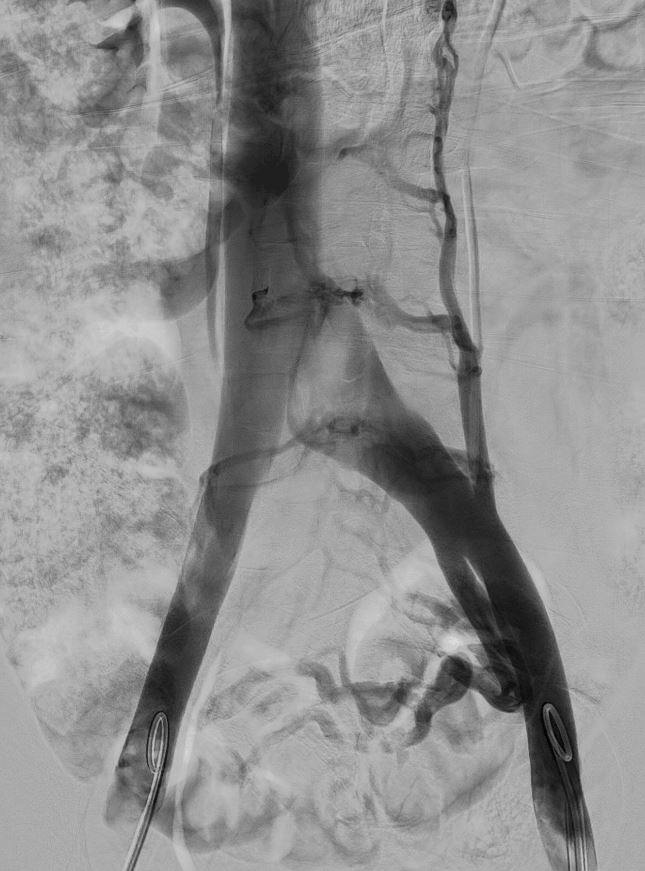

- Arteriography

A minimally invasive diagnostic technique providing anatomical and dynamic information about arteries. It allows immediate treatment with angioplasty when necessary.

- Phlebography

A minimally invasive diagnostic test offering high-quality images of vein morphology and flow. Pelvic or iliocavography phlebography can measure pressure gradients and perform embolization treatments during the same session.